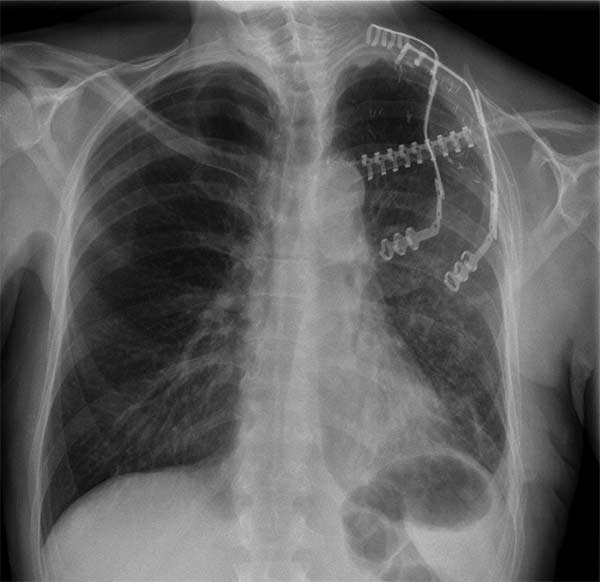

Surgery was performed with curative intent. The patient was positioned supine with the neck fully extended and the head turned away from the tumor. The tumor was approached through the anterior trans-cervical approach described by Dartevelle. This approach allowed us to dissect the subclavian vascular bundle and the nerve roots of the brachial plexus freely, quickly and safely without sacrificing the radical intent of the operation. After assessing the extent of the tumor from inside and outside of the chest, the lateral arches of the first, second and third ribs were cut and removed en-bloc with the surgical specimen (Figure 2). Due to the high risk of de-stabilizing the shoulder girdle after resection of the first three ribs, clavicle division and muscle resection, we reconstructed the chest wall and clavicle using the Stratos™ titanium bars and clips (Strasbourg Thoracic Osteosyntheses System; MedXpert, Heitersheim, Germany) (Figure 3). The chest wall defect and the reconstructed clavicle were covered with polytetrafluoroethylene (PTFE) patches (Figure 4).

During follow-up the respiratory function and dynamics were optimal and there was no mechanical failure of the titanium bars and clips. The surgical margins were free from disease, and after 6-months follow-up the patient is free from disease recurrence.